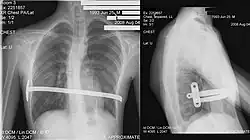

X-Ray of a 15-year-old male after undergoing the procedure

Through two small incisions in the side of the chest, an introducer is pushed along posterior to the sternum and ribs, and anterior to the heart and lungs. Then a concave stainless steel bar is slipped under the sternum, through the incisions in the side of the chest. A third, smaller incision is made to insert a thoracoscope (small camera) used to help guide the bar. Taller patients, older patients, or patients requiring extensive correction may receive two or more bars. All bars may be placed through two incisions or additional incisions may be made. The bar is then flipped, and the sternum pops out. To support the bar and keep it in place, a metal plate called a stabilizer may be inserted with the bar on one side of the torso. PDS sutures may also be used in addition to the stabilizer. The stabilizer fits around the bar and into the ribcage. The bar and stabilizer are secured with sutures that dissolve in about six months.